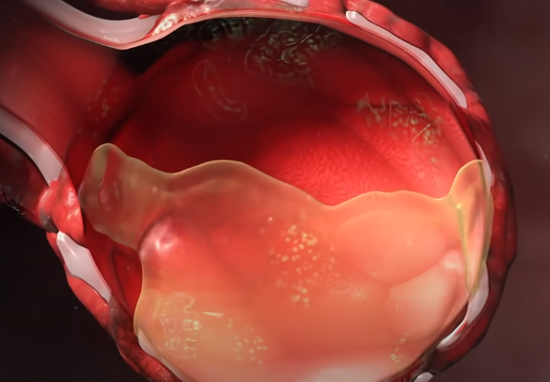

但是,由于战斗的持续,血管通透性增强,血液渗入肺泡,同时在肺泡内会分泌大量黏液。

如果在这个时候,对患者肺部进行CT扫描,我们会看到像下面这样大面积白色区域,医学上称之为“白肺”。这样肺部失去了原有的交换气体功能,最终使正常呼吸变得异常困难。

千疮百孔的肺部会成为病毒进一步攻击的有利条件,它们会通过血管进入血液循环系统,而细胞因子会紧随其后。